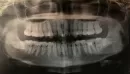

Нужно исправить как-то внешний вид передних зубов. Единица слева - наклонная в рот, а двойка - вверх к губе. Брекеты ставить не хочу, нужно вырывать много зубов. Да и не смогу ходить с ними два года, как говорят врачи.

Может проще вырвать двойку? Или винир, люминир установить?